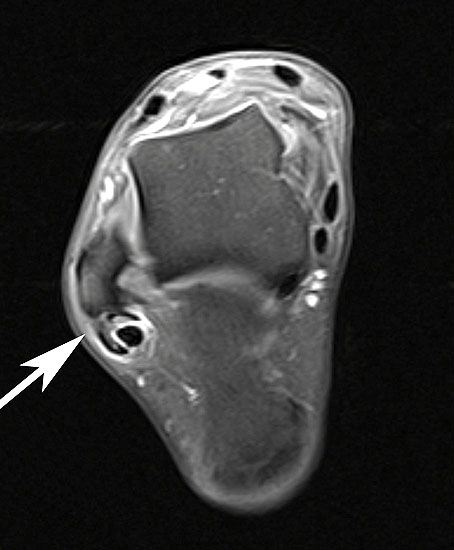

MRT mit KM bei Split der Peronaeus brevis Sehne in Höhe der Fibulaspitze

Abbildung 13

Klassischerweise beginnt eine Peronealsehnenruptur mit einem Distorsionstrauma. Bei dieser Verletzung kommt es zunächst zu einer Längsruptur (Peroneus-Split) der Peronaeus brevis Sehne in Höhe der Fibulaspitze. Bestehen nun Risikofaktoren wie eine persistierende Instabilität des Sprunggelenks oder ein bis zu diesem Zeitpunkt asymptomatischer Rückfußvarus, kommt bei jeder weiteren Distorsion zu einer Zunahme des Sehnenschadens bis hin zur vollständigen Kontinuitätsunterbrechung 38. Für das Peronaeus Split Syndrom gibt es kein klassisches Leitsymptom. Wichtig ist bei anhaltenden Beschwerden nach einem Distorsionstrauma an diese Differentialdiagnose zu denken und ein MRT mit Kontrastmittel zu veranlassen 39.